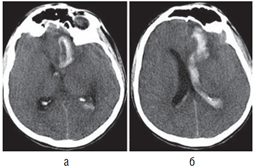

Внутримозговые гематомы, помимо этиологии, подразделяют по локализации и объему. В подавляющем большинстве случаев (до 90%) гематомы локализуются в супратенториальных отделах мозга. Различают лобарные, латеральные, медиальные и смешанные внутримозговые гематомы (рис. 12.1).

• Лобарными называют кровоизлияния, при которых кровь не выходит за пределы коры и белого вещества соответствующей доли или долей головного мозга.

• Кровоизлияния в подкорковые ядра (кнаружи от внутренней капсулы) принято обозначать как латеральный инсульт, а кровоизлияния в таламус — как медиальный инсульт (кнутри от внутренней капсулы).

• На практике чаще всего встречают смешанные внутримозговые гематомы, когда кровь распространяется в пределах нескольких анатомических структур.

Рис. 12.1. Внутримозговые гематомы разных локализации и объема (компьютерная томограмма): а — небольшая смешанная внутримозговая гематома правого зрительного бугра, внутренней капсулы и подкорковых ядер; незначительная компрессия и смещение задних отделов III желудочка влево; б — внутримозговая гематома правой теменной доли, средних размеров; умеренное смещение срединных структур влево; в — большая смешанная внутримозговая гематома передних отделов левого полушария с прорывом в правый боковой желудочек; выражены компрессия и дислокация мозга вправо

Объем внутримозговых гематом при геморрагическом инсульте может варьировать в очень широких пределах — от нескольких миллилитров до 100 мл и более (см. рис. 12.1, 12.2). Существуют различные способы определения объема гематомы. Наиболее простой из них — способ расчета объема по данным КТ с использованием следующей формулы: максимальная высота × максимальная длина × максимальная ширина : 2. Распределение гематом по объему весьма условно. Принято деление на небольшие (до 20–30 мл), средние (до 50–60 мл) и большие (>50–60 мл) гематомы. Небольшие, средние и большие гематомы встречаются приблизительно с одинаковой частотой.